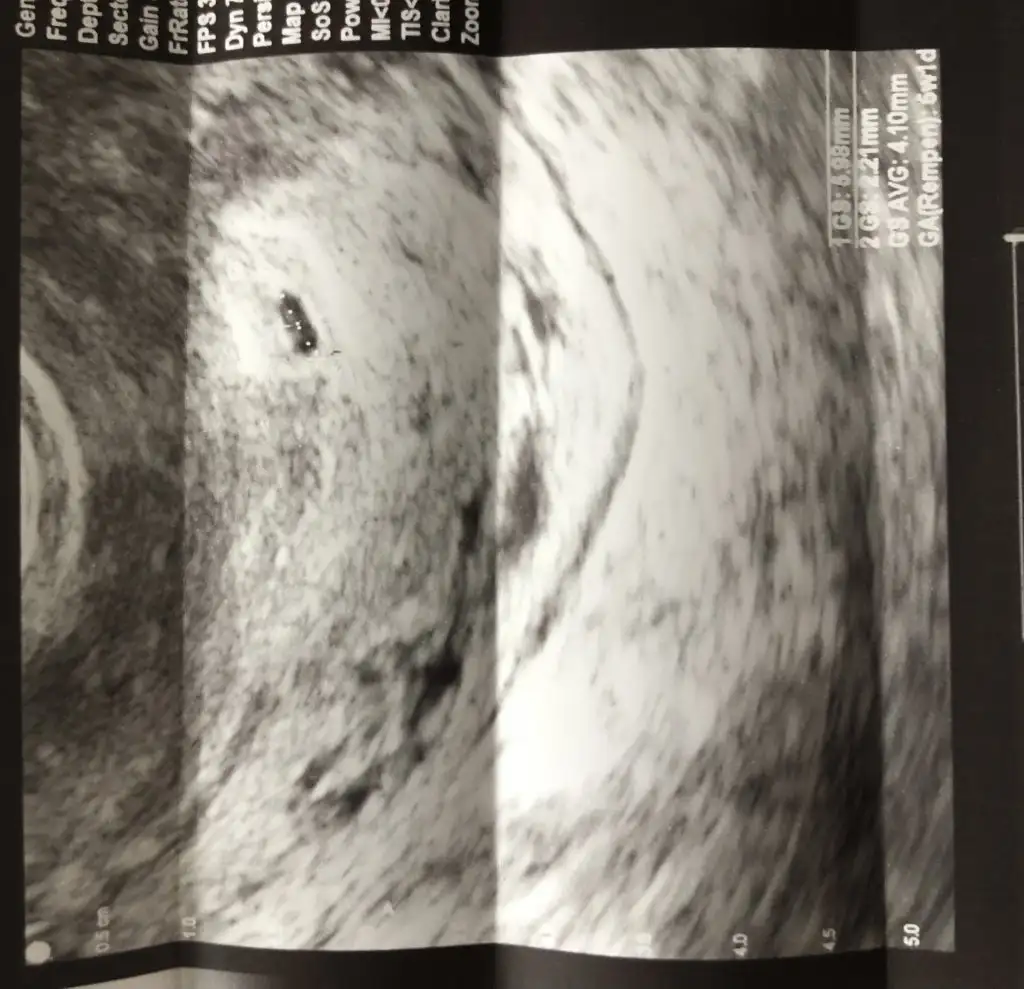

Bana alttan bakıldı o yüzden mi bilmiyorum mm yazmıyor doktor da söylemediCanım hayırlı olsun bende 5+1 de gördüm kese dün 3.70mm yazıyordu bana çok küçük geldi sende kaç mm yazıyor :)

Canım hayırlı olsun bende 5+1 de gördüm kese dün 3.70mm yazıyordu bana çok küçük geldi sende kaç mm yazıyor :

GS Yazanlar olmalı ama çok gs yazıyor bilemedim:)Eki Görüntüle 3023650

Bende bilemedim canımGS Yazanlar olmalı ama çok gs yazıyor bilemedim:)